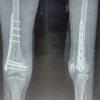

Results: The mean follow-up in the present study was 6 months. All fractures were united with a mean union period of 18.2 weeks. At final follow-up, fixed flexion deformity was seen in 25% of the patients. There were 16 cases of infection with 2 being a superficial infection treated conservatively and 14 cases having a deep infection treated with debridement and antibiotics. 2 cases of nonunion, 4 cases of malunion and 4 cases of delayed union were observed. 16 cases develop joint stiffness. 16 cases also developed limb shortening and 10 had fixed flexion deformity and 8 had varus deformity. At the time of final follow-up through "SCHATZKER AND LAMBERT SCORING SYSTEM," satisfactory outcomes were achieved in 50% (20.8%excellent and 29.2% good) of the patients.

Conclusion: Distal femur fracture treated with anatomical LCP needs careful anatomical reduction, rigid fixation and early knee mobilisation and weight bearing on signs of healing with an early presentation to the hospital from the time of injury were the essential factors in achieving better outcome for the patient.